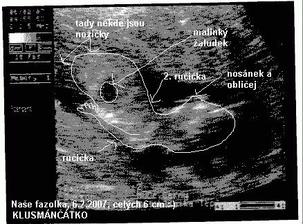

SRPŇÁTKA 2007 - fotky UTZ

album věnované mimískům, které se narodí v srpnu 2007 a jejich maminkám ze "Společného termínu SRPEN"